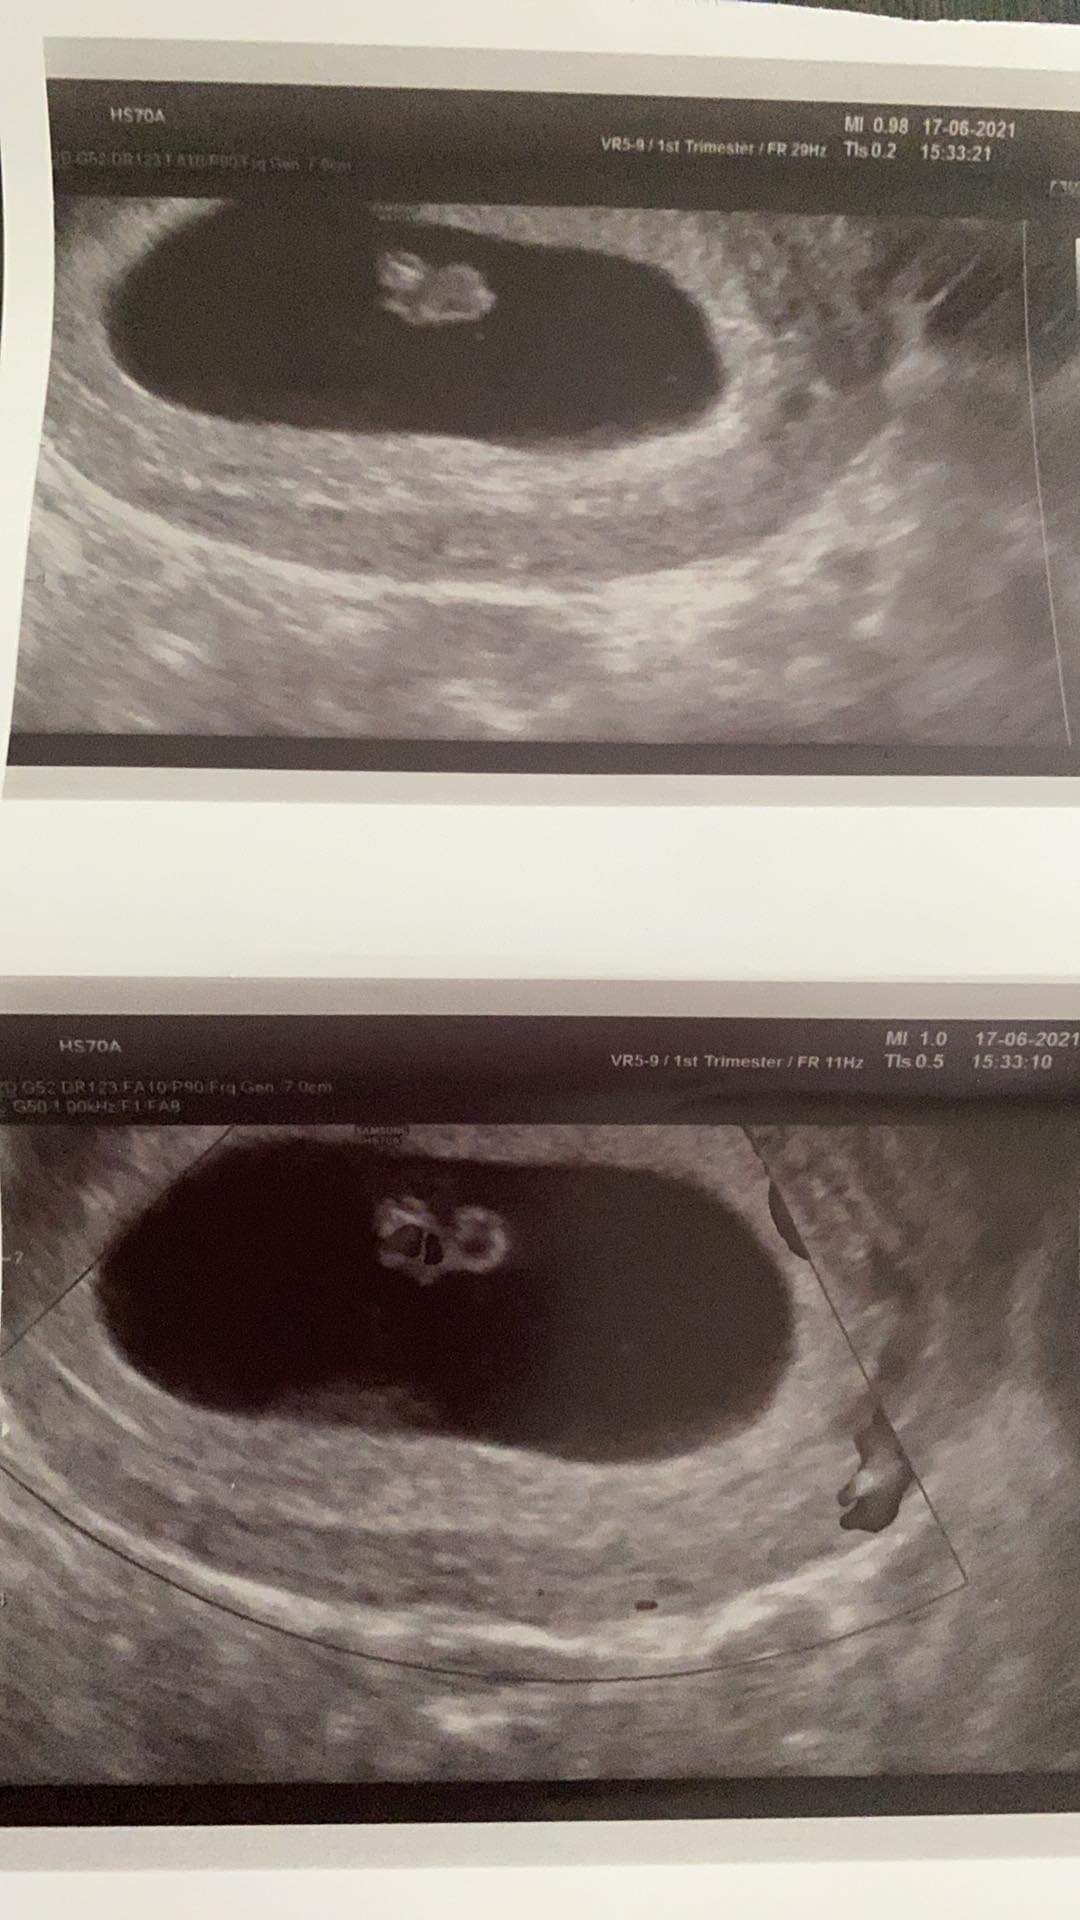

Hej dziewczyny właśnie wróciłam z USG 6/7 tydzień 🙂 serduszko bije jak dzwon zarodek ma 6-7 mm także bardzo się cieszę ! Kolejna wizyta za 3 tygodnie😃🥰

Załączniki

• 8C6B2EFD-0F41-43F7-8C3C-7FA9F15C3171.jpeg

8C6B2EFD-0F41-43F7-8C3C-7FA9F15C3171.jpeg

234,8 KB · Wyświetleń: 123